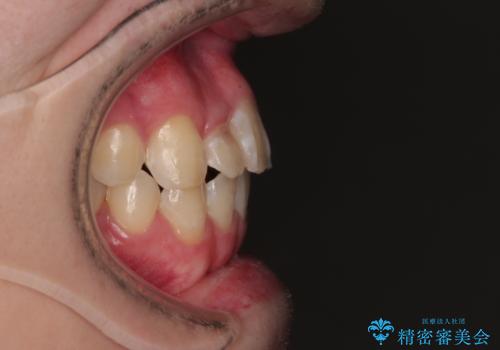

初診時の状態

・上下ともに歯がきれいに並びきらず、がたつきが見られました。

・上下の前歯の中心(正中)がずれています。

・特に上顎の幅が狭いため、下顎の歯列も内側に入り込み、歯が並ぶスペースが不足していました。